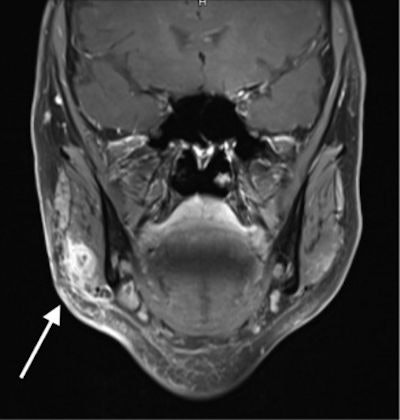

An ultrasound scan revealed an approximately 20 x 15-mm encapsulated mass. Clinicians started the patient on intravenous ampicillin/sulbactam due to the closeness of the mass to the facial nerve, and an MRI scan was performed. MRI showed a polylobulated lesion that measured 13 x 10 x 15 mm in the right masseter muscle, a facial muscle that plays a major role in chewing.